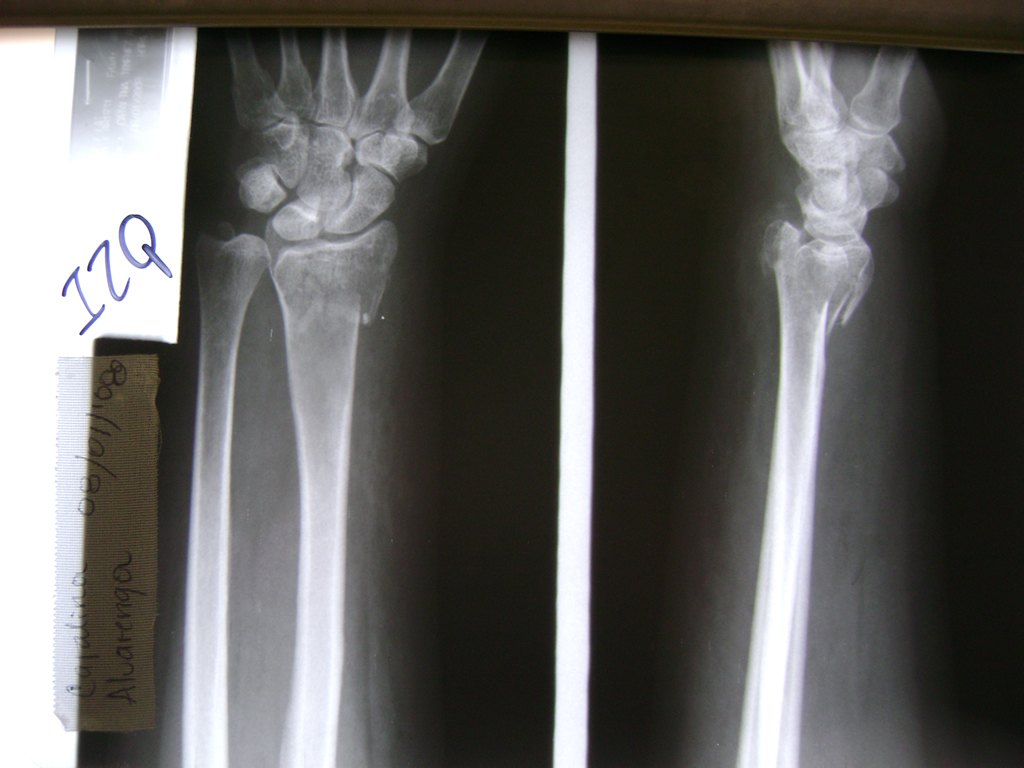

Cirugías de Muñecas

Los procedimientos más comunes en cirugía de la mano son aquellos destinados a reparar traumatismos, incluyendo lesiones de tendones, nervios, vasos sanguíneos, y articulaciones; huesos fracturados; y quemaduras, cortes, y otros daños de la piel.